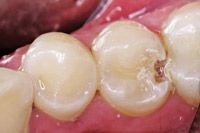

The patient presents with a mandibular premolar with a large distal carious lesion (Figs. 1 and 2).

Fig. 2